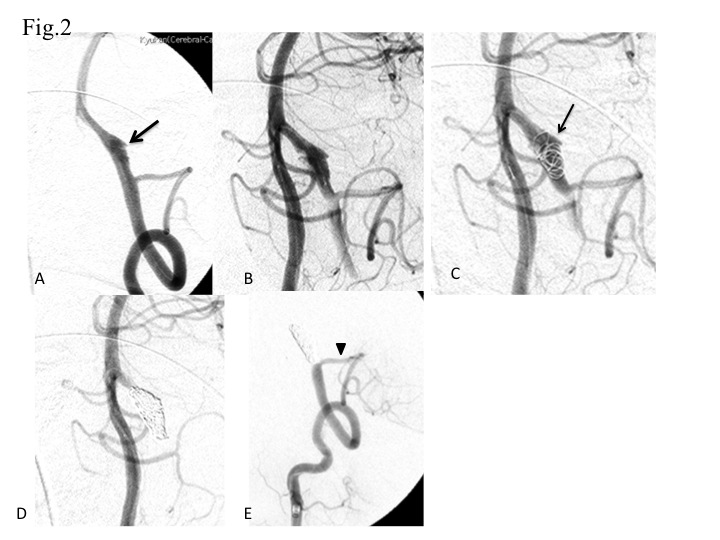

Methods- Nineteen patients with ruptured VADA received endovascular treatment in the acute stage. Among them, 17 were treated by internal trapping of the dissected segment. We performed stent-assisted coiling for a case of VADA in the contralateral hypoplastic VA and a case of bilateral dissection (ruptured VADA of the right VA and dissection of the left VA).